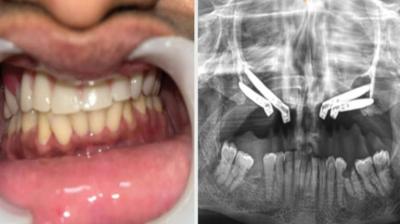

एम्स भोपाल डेंटल टीम ने लिखा इतिहास, इंटरनेशनल जर्नल में केस भेजा

एम्म में जटिल सर्जरी को सफलतापूर्वक अंजाम दिया है। इस सर्जरी में ट्यूमर के कारण काटे गए निचले जबड़े को पैर की हड्डी से दोबारा बनाया गया और उसमें 13...